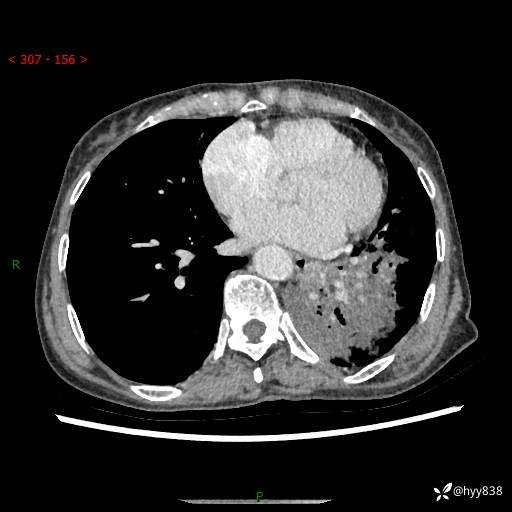

胸部CT平扫+增强